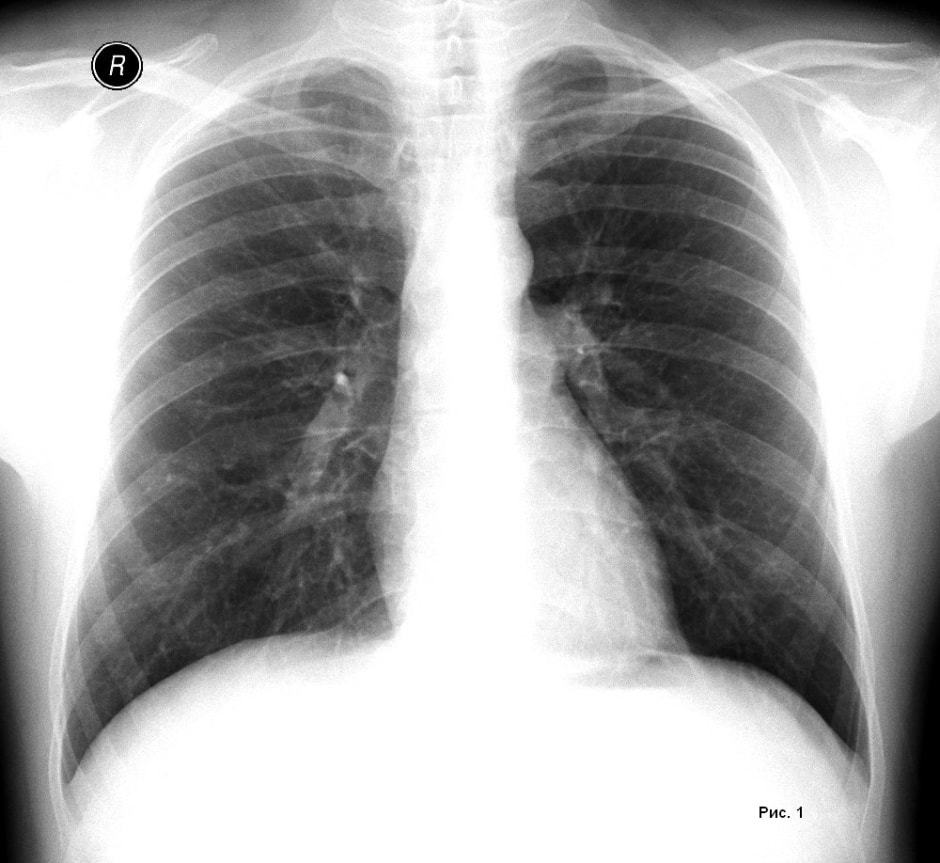

Команда установила, что воспаление, вызванное респираторной вирусной инфекцией, пробуждает так называемые диссеминированные раковые клетки (ДРК), которые могут годами сохраняться в тканях организма, не проявляя активности. В частности, это касается клеток рака молочной железы, “спящих” в легких.

В эксперименте на лабораторных моделях метастатического рака у мышей ученые наблюдали, как после заражения SARS-CoV-2 или вирусом гриппа происходило быстрое пробуждение ДРК в легочной ткани и формирование метастазов в течение двух недель.